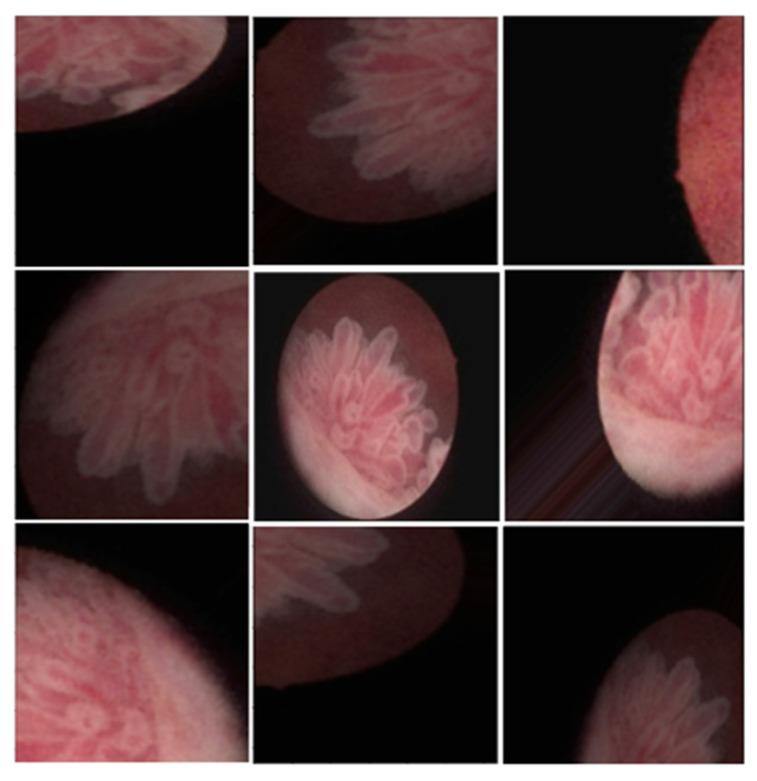

The dataset was split into training and validation sets with a 4:1 ratio. The VGG19 classification model achieved an accuracy score of 0.912. The Deeplab v3+ segmentation model achieved an IoU of 0.833 and a binary accuracy of 0.951. Visual analysis revealed a high similarity between the lesions identified by Deeplab v3+ and those labeled by experts.

数据集按4:1的比例分为训练集和验证集。VGG19分类模型的准确率得分为0.912。深度Lab v3+分割模型的IoU为0.833,二元准确性为0.951。视觉分析显示,深度Lab v3+识别的病变与专家标记的病变高度相似。